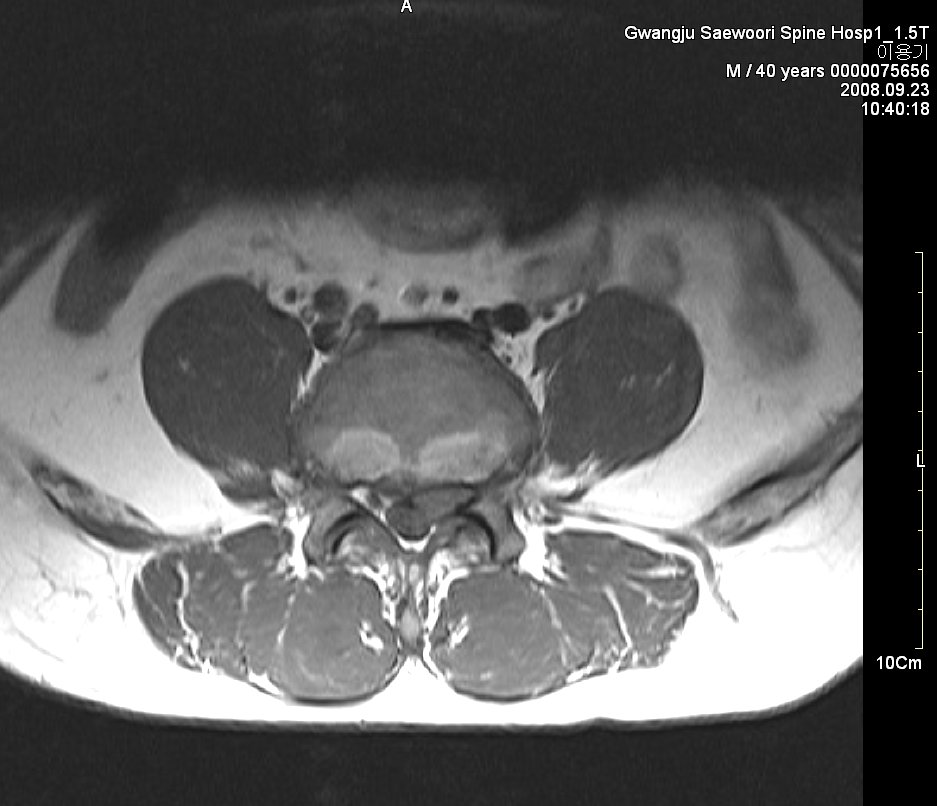

그림. sequestration사진. 월산동 남편 mri

그림. 흡수된 사진

symptom : local low back pain, lt buttock pain, lt leg radiating pain 허리에서 엉덩이 종아리까지 쑤시고 애림. 야간에는 통증으로 잠을 못 이룸.

sign : l5 sensory impairment, motor nerve intact(manual muscle powr test - nonspecific), dtr(++/++)

evidence : l-spine mri 사진

치료과정

침상안정 3일, 3일동안 허리 얼음찜질 1시간 30분씩 하루 5회 시행,

제가 2년 전 월산원광한방병원에서 치료한 환자 사진입니다. 수술을 위주로 치료하는 의사가 판단하기에 황당하게 보일지 모르겠습니다. 하지만 이 환자는 현재 가끔 골프도 치면서 허리디스크를 앓기 전보다 더 건강한 허리를 가지고 살아가고 있습니다.